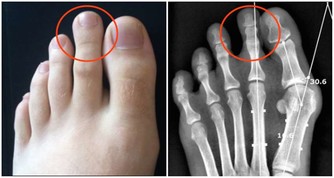

3、胃息肉:腺瘤型或絨毛型息肉,雖然佔胃息肉中的比例不高,癌變率卻為15%~40%。直徑大於2cm者癌變率更高。增生性息肉多見,而癌變率僅1%。